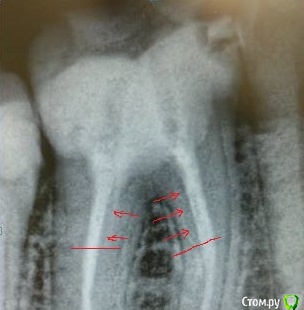

DmitrySH Опубликовано 19 мая, 2015 Поделиться Опубликовано 19 мая, 2015 На Рвг кажется, что свш вообще до каналов не доходят Ссылка на комментарий

Ico Опубликовано 20 мая, 2015 Поделиться Опубликовано 20 мая, 2015 (изменено) в средней трети.Скорее всего это были глассиксы паленые,поэтому так легко разволокнялись. Изменено 20 мая, 2015 пользователем Ico Ссылка на комментарий